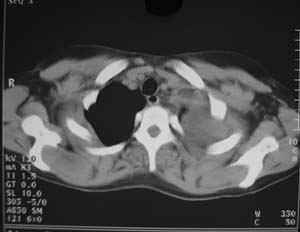

支持骨肉瘤肺纵隔胸膜转移。

骨肉瘤胸膜及肺内转移

支持骨肉瘤并胸膜及纵隔多发转移。